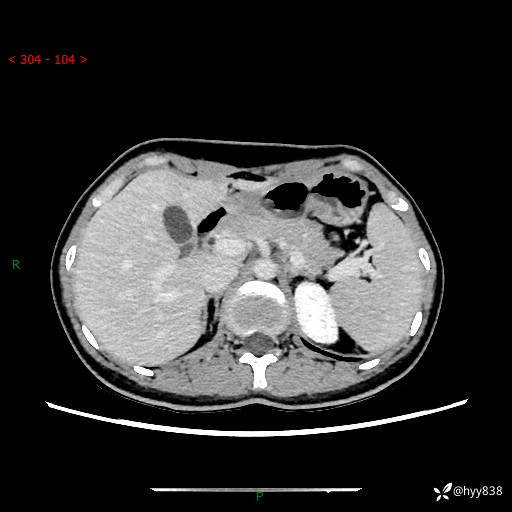

性别:女

年龄:23岁

简要病史:外院发现肝结节,来我院进一步增强确诊

上腹部CT平扫+增强

肝囊肿 (68)